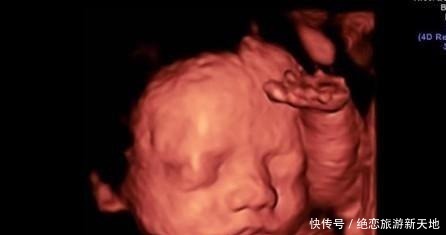

1.实时观察胎儿动态运动,检查胎儿生长发育情况。在怀孕期间,孕妈妈可以通过四维彩超得知胎儿在宫内的一些动态情况。比如说,通过四维彩超能够清楚的看到胎儿在宫内吞吐羊水,眨眼睛,吮吸手指,做鬼脸等动作。医生还可以通过四维彩超更清楚的看得到胎儿的发育情况,比如说血管畸形,体表畸形,内脏畸形等等,提前得知胎儿是否有唇裂,脊柱裂,骨骼发育不良,先天性心脏病等疾病,做到早知道早干预早治疗。2.图像清晰逼真。四维彩超相对于三维彩超更高清更精确,所以看起来更清晰,很多孕妈妈在做四维的时候就可以清晰地看到胎儿的五官,可以初步的判断一下胎儿到底长得像准爸爸还是准妈妈,所以,四维彩超也成为胎儿人生中的第一张照片。而不像二维一样,在大部分人看来就是黑坨坨的一片。【孕期做四维有什么好处,什么时候做最好这个时候做是最好的】

最适合做四维彩超的是怀孕24周,①在孕22周的时候胎儿的身体各个器官已经发育完成,到了怀孕24周的时候更完善了。②怀孕24周的胎儿还并不是很大,大约只有630克,身长也只有30cm左右。③怀孕24周的羊水大约500到700ml左右,虽然还不是羊水最多的时候,不过这时候胎儿比较小,相比起来空间还是很大的。在怀孕24周的时候,胎儿比较小,羊水相对起来比较多,胎儿有足够的空间自由翻滚,在做四维彩超的时候也会比较方便观察胎儿正面和背面情况。